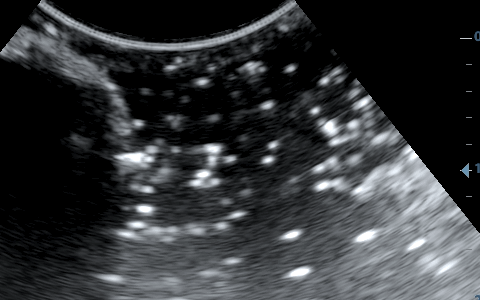

2) Το βάθος (depth), δηλαδή το να φέρουμε στην οθόνη του υπερήχου όσο το δυνατόν πιο κοντά το αντικείμενό μας, ώστε να καλύπτει σχεδόν τα 2/3 της οθόνης μας.

Μειώνουμε το βάθος ώστε να φέρουμε κοντά μας το αντικείμενο.

3) Τη συχνότητα, δηλαδή όσο πιο μεγάλη είναι αυτή, τόσο πιο πολλές λεπτομέρειες βλέπουμε αλλά ταυτόχρονα αυξάνονται τα τεχνουργήματα από αέρα και άλλες δομές. Οι αρμονικές βοηθούν στην καταστολή αυτών των τεχνουργημάτων.

4) Το focus, δηλαδή την εστίαση της δέσμης, όσο πιο κοντά βρίσκεται σε αυτό που θέλουμε να μελετήσουμε τόσο καλύτερη εικόνα έχουμε.